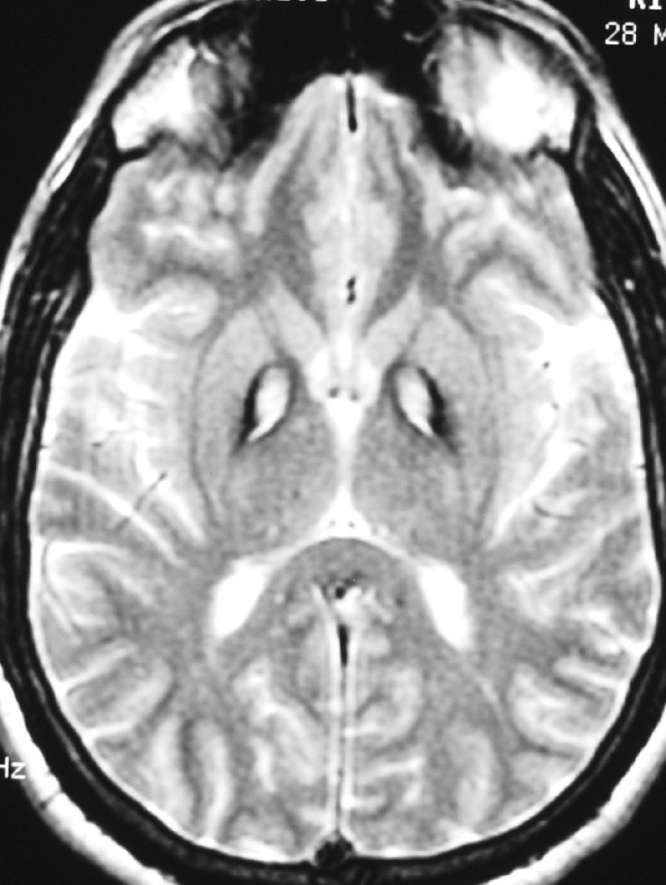

An MRI scan of the brain demonstrated central hyperintensity with surrounding hypointense signal in globus pallidus, bilaterally suggestive of “eye of the tiger” sign on FLAIR (Fig. 1) and T2-weighted (Fig. 2) sequences.

Figure 2.

27-year-old patient with pantothenate kinase 2 deficiency. T2-weighted MRI image shows “eye of tiger” sign with hyperintense center and hypointense periphery in globus pallidus bilaterally.